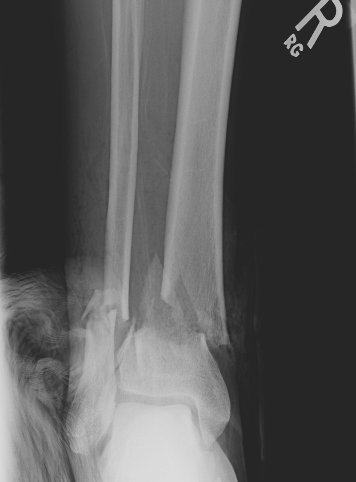

Return to Tibia and Fibula Fractures